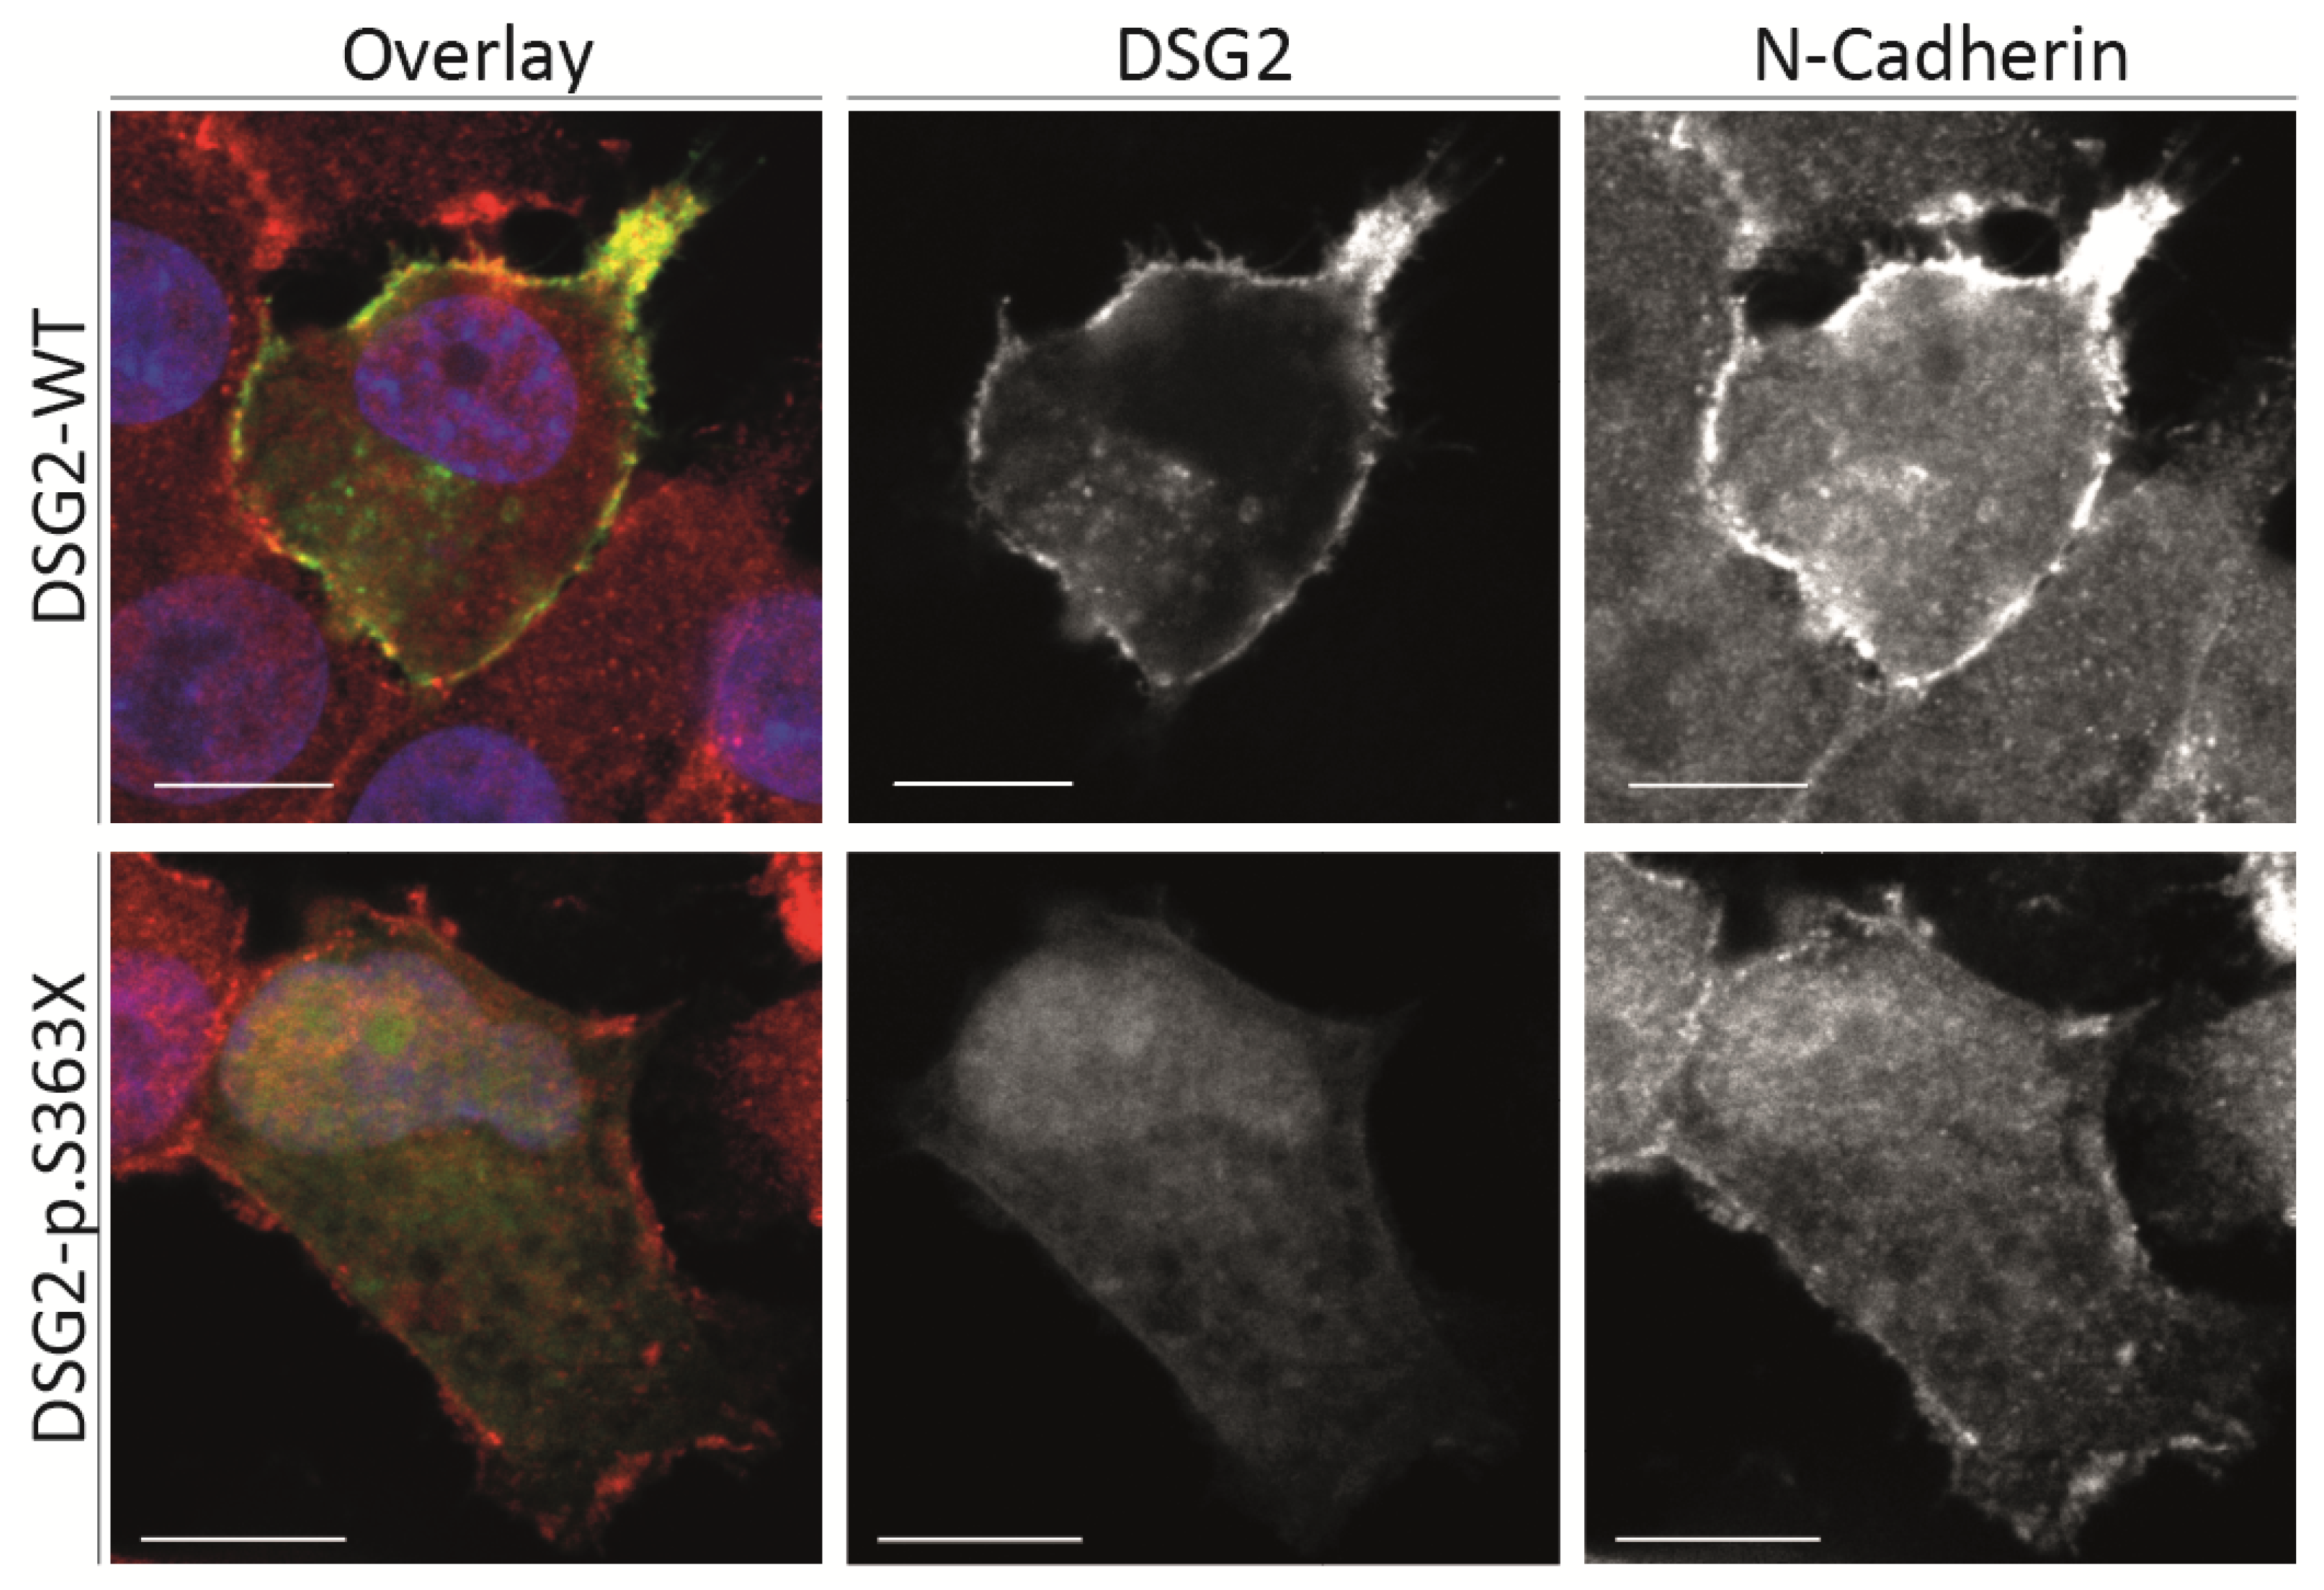

2.3. Cell Culture Experiments